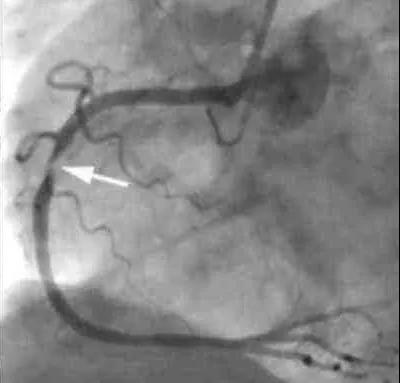

這位患者就到我們醫院住院了。這個患者沒有典型的勞累時胸悶或者胸痛癥狀,但有頸部緊縮感,再看看他的耳朵,確實有明顯的皺褶,很有可能是冠心病。做冠脈造影,果不出所料,心臟三根血管均有狹窄,右冠脈重度狹窄,植入一枚支架。